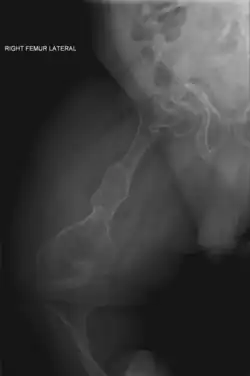

The main symptom of osteogenesis imperfecta is fragile, low mineral density bones; all types of OI have some bone involvement.[5] In moderate and especially severe OI, the long bones may be bowed, sometimes extremely so.[28] The weakness of the bones causes them to fracture easily—a study at the Endocrine Unit at the National Institute of Child Health in Karachi, Pakistan found an average of 5.8 fractures per year in untreated children.[29] Fractures typically occur much less after puberty, but begin to increase again in women after menopause and in men between the ages of 60 and 80.[1]: 486

Diagnosis is typically based on medical imaging, including plain X-rays, and symptoms. In severe OI, signs on medical imaging include abnormalities in all extremities and the spine.[97] As X-rays are often insensitive to the comparatively smaller bone density loss associated with type I OI, DEXA scans may be needed.[5]: 1514

In those with type III OI who had undergone rodding surgery, 79.5% had the femurs and tibias of both legs rodded.[25]: Table I The most common form of rods used are intramedullary (IM) rods, some of which, such as the Fassier–Duval IM rod, are telescoping, meaning that they are designed to grow as the child grows, in an attempt to avoid the necessity of revision surgeries.[118] Telescoping IM rods are widely used,[119] and the common Fassier–Duval IM rod is designed to be used to rod the femur, tibia, and humerus.[120]: 1 The surgery involves breaking the long bones in between one and three (or more)[119]: Figure 4 places, then fixing the rod alongside the bone to keep it straight.[120]: 11